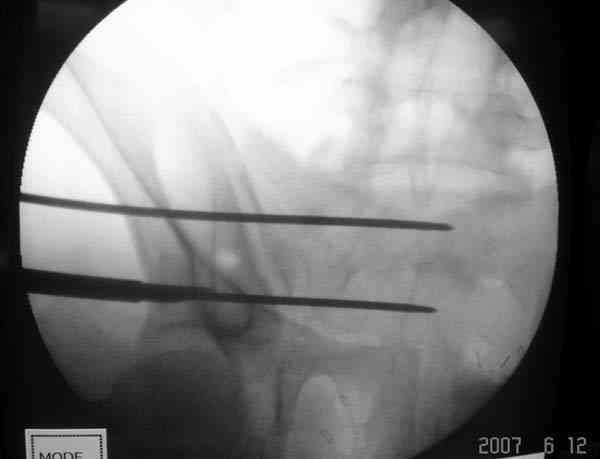

Применение длинных (7 мм каннюлированных, с резбой на всем протяжении от компании Mercury) шурупов, проведенных между двумя илиосакральными сочленениями нейтрализирует деформацию до наступления сращения.

На другом конце затягивание гайкой создает эффект болта-стяжки.

Сверло-направитель в 3.2 мм проводится вручную без применения дрели, и длина в 46 см обычно достаточна до захвата следующего илио-сактрального сочленения.

Sacroiliac screw placement

Inlet view

Проведение сверла под неврологическим мониторингом уменьшает риск повреждения нервов во время операции.

SI potential monitoring